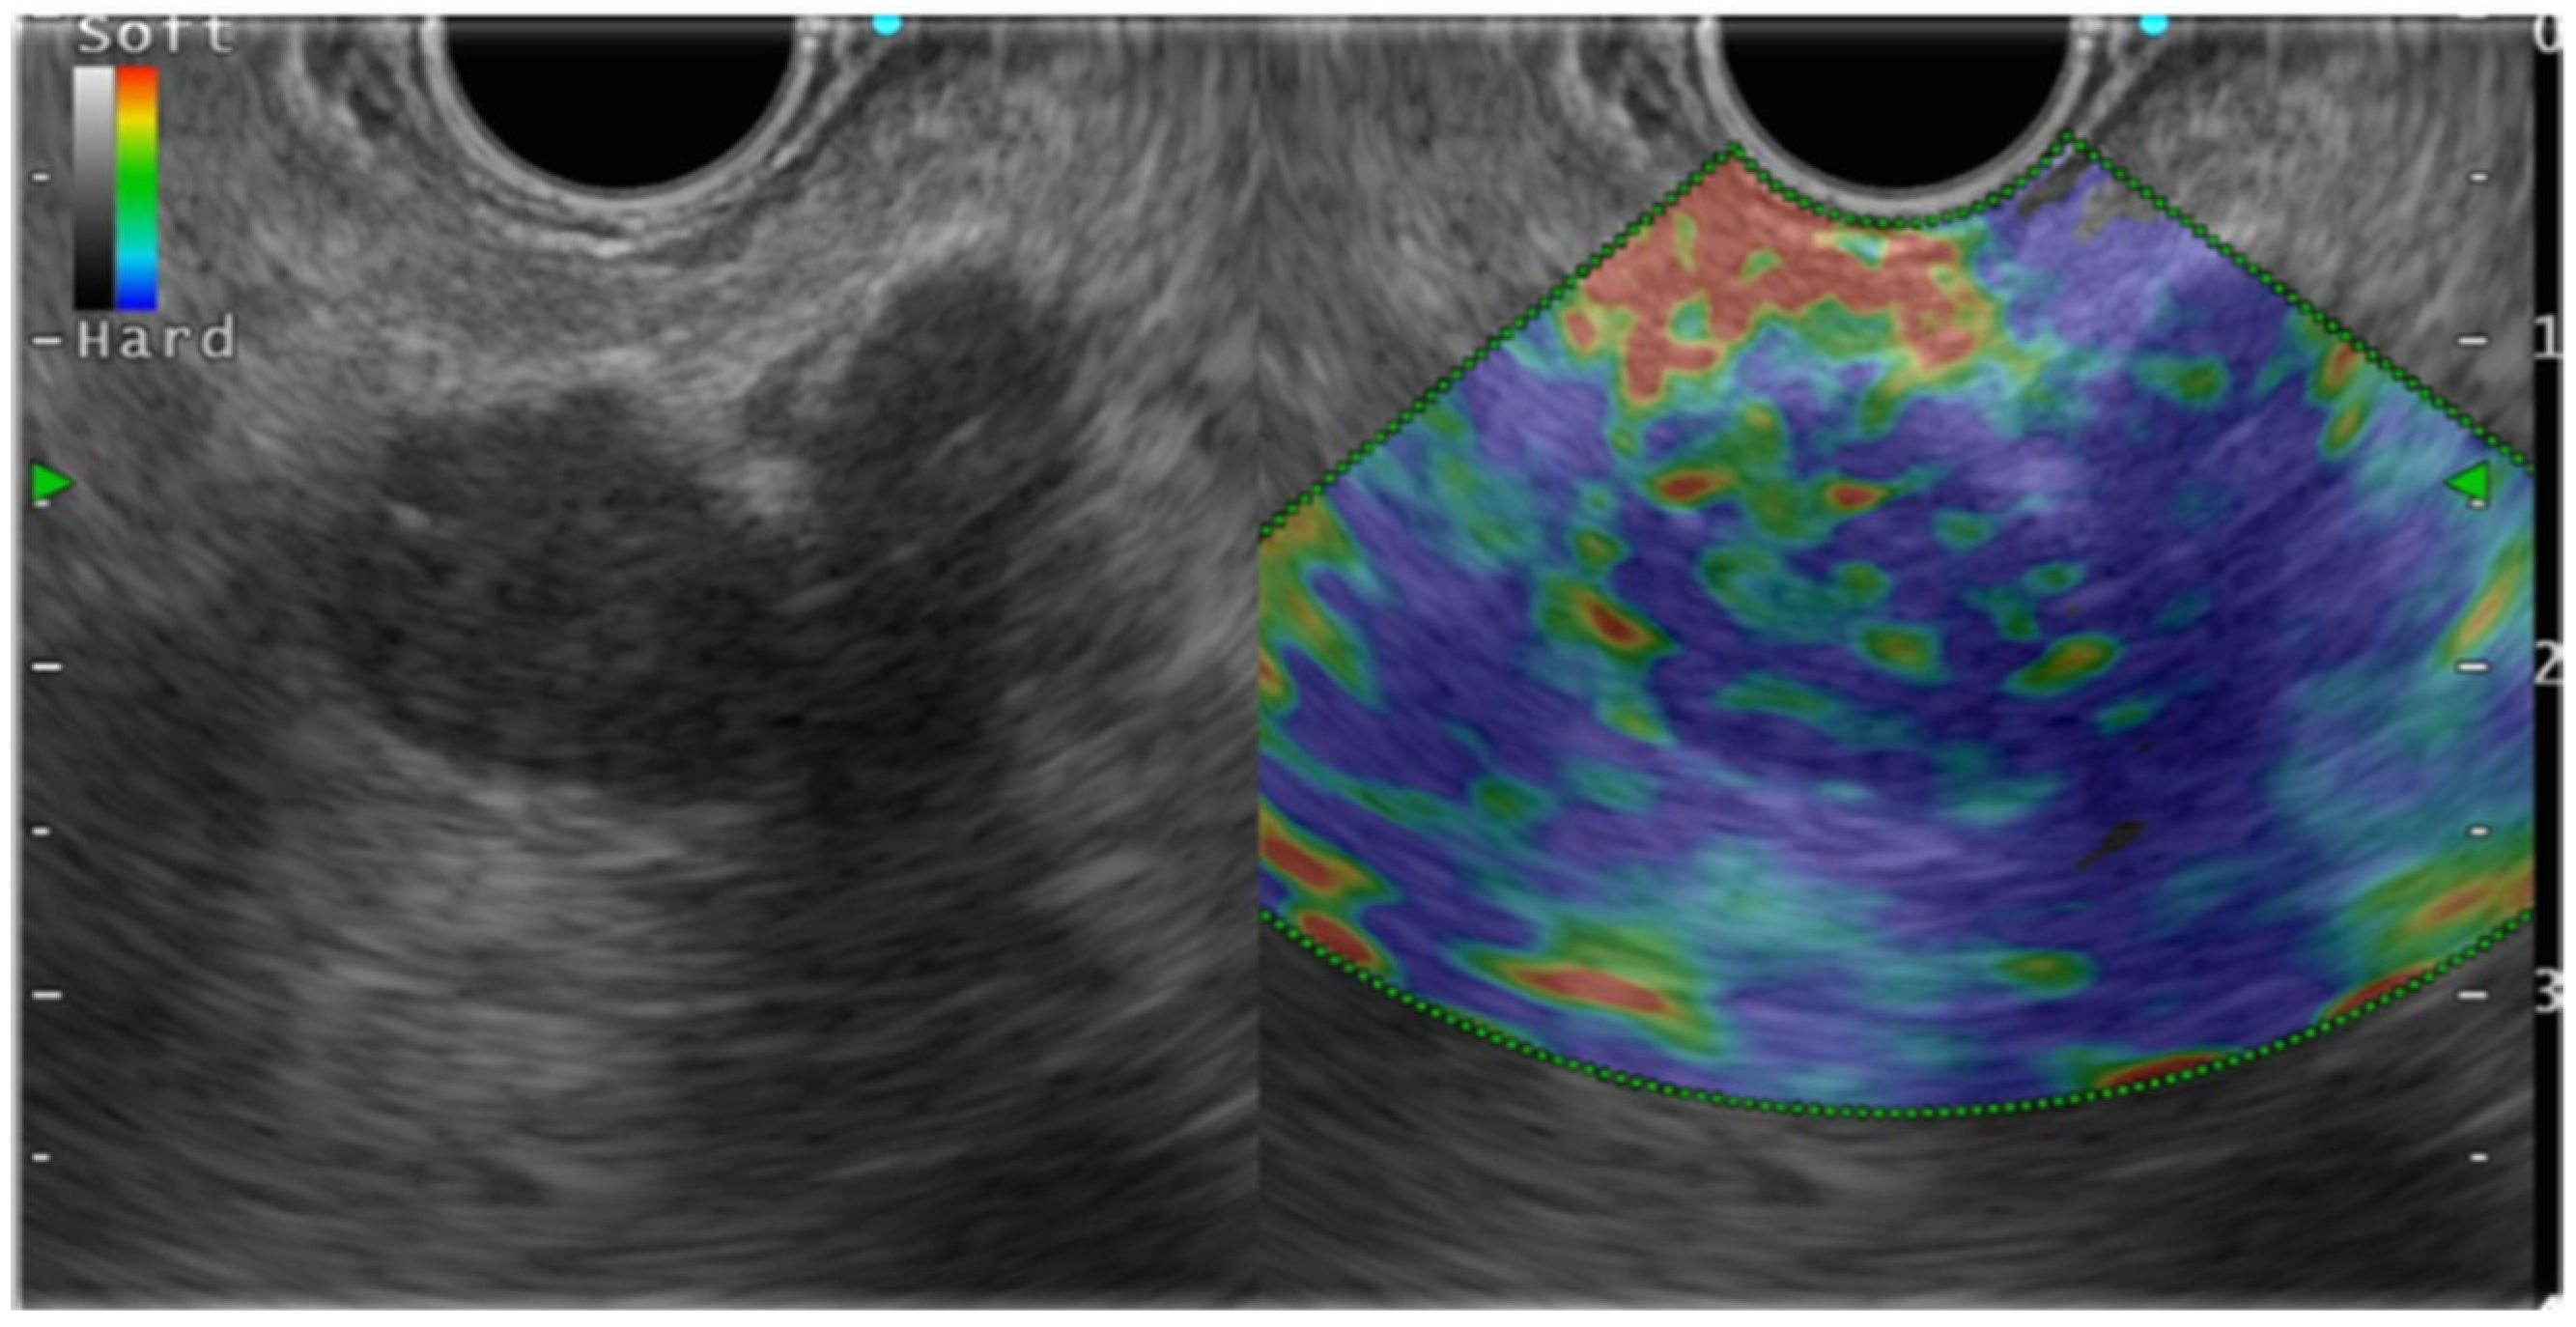

In fact, CP has a higher degree of hardness than a normal pancreas (Figure 2). Generally speaking, CP appear as blue and heterogeneous on EUS-EG as the disease progresses, which correlates with the Rosemont classification [11,15,20]. Kim et al. have described a mean SR of 3.78 ± 1.35 for a normal pancreas and 8.21 ± 5.16 for CP. Using a cut-off value of 5.62, the sensitivity, specificity, and accuracy of SR for detecting CP were, respectively, 72%, 75%, and 75% [21]. Several published reports have described the usefulness of EUS-EG for CP (Table 1).

Figure 2.

Endosonography (EUS) elastography in chronic pancreatitis.